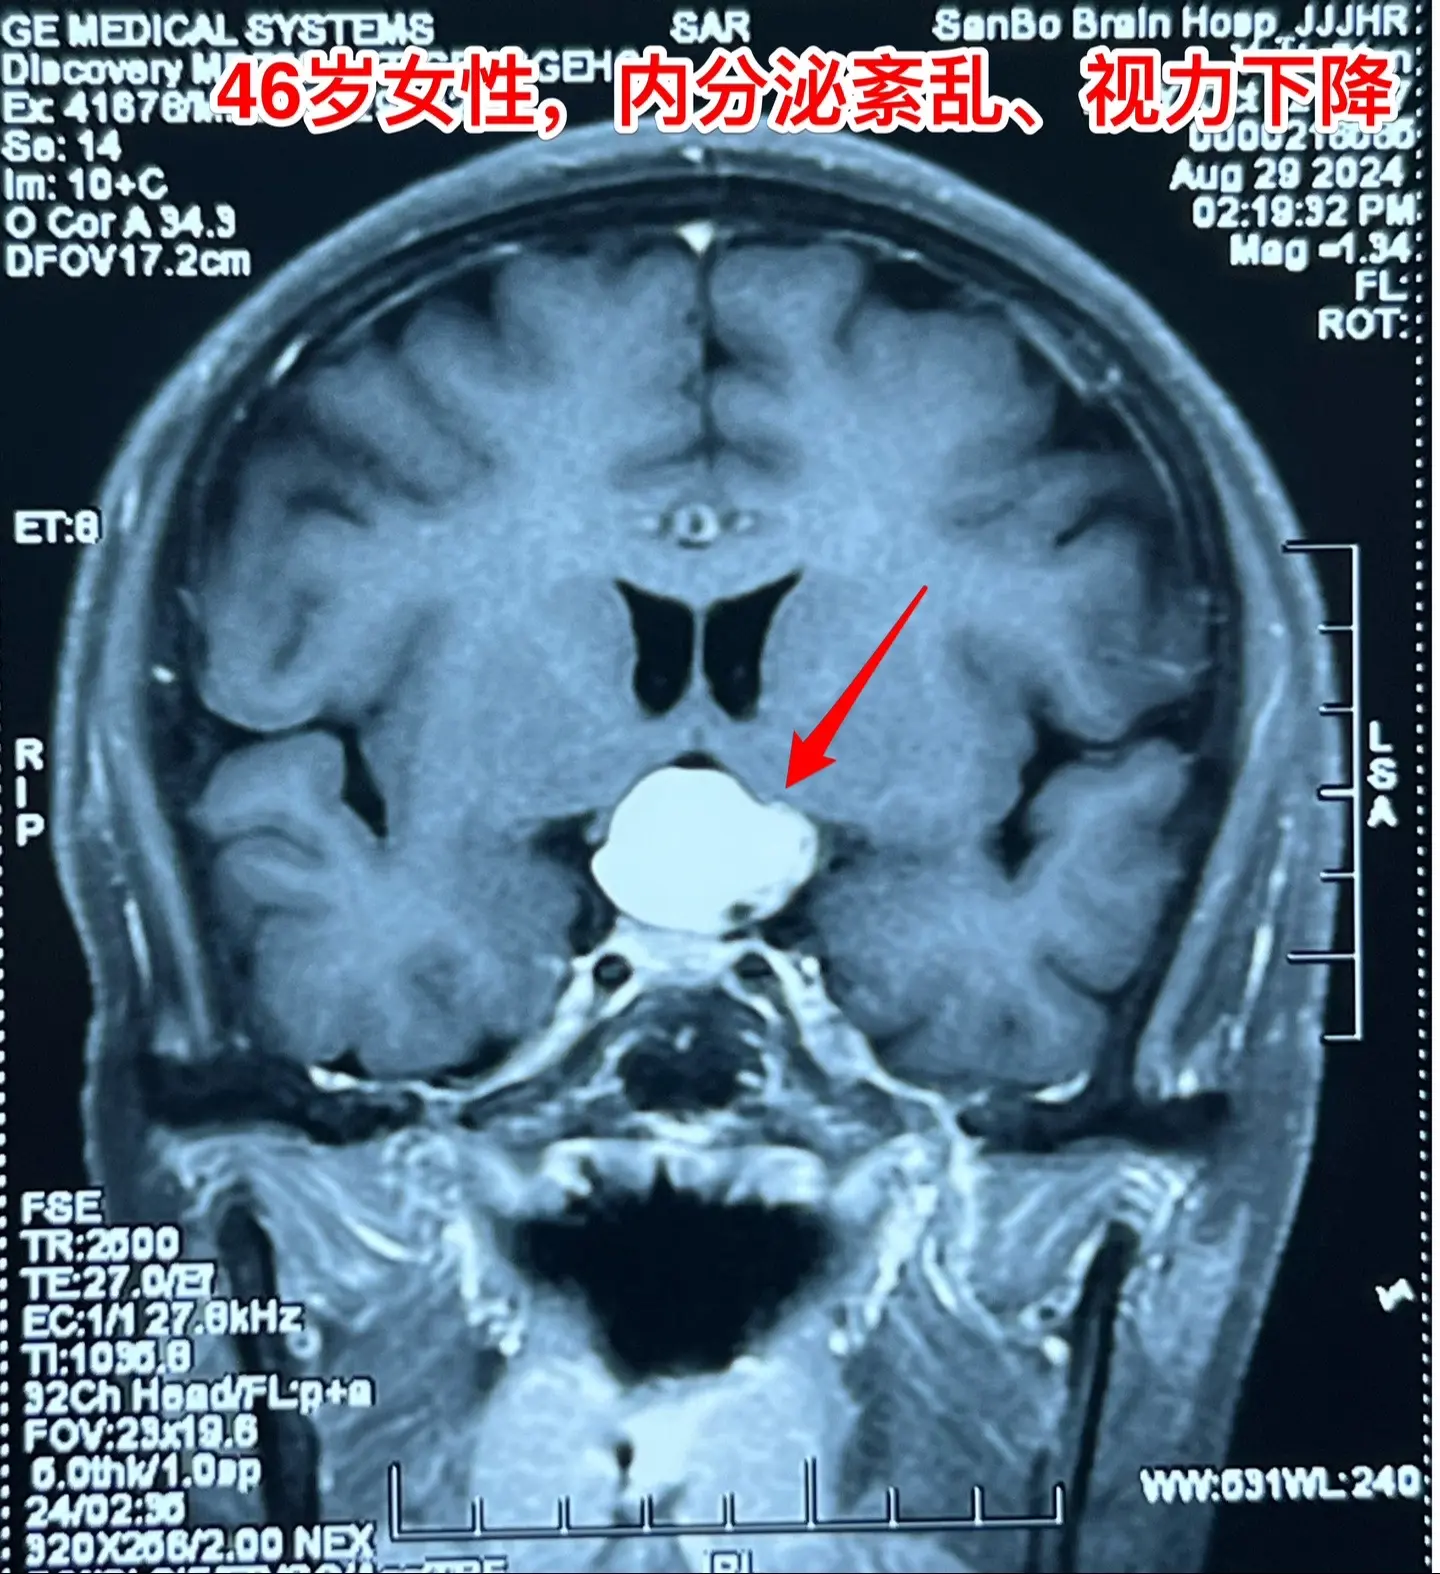

颅咽管瘤与拉克氏囊肿好鉴别吗?典型的造釉细胞型颅咽管瘤有钙化,与拉克氏囊肿容易鉴别。 典型的乳头型颅咽管瘤有明显的强化灶,与颅咽管瘤也好鉴别。 不典型的颅咽管瘤与拉克氏囊肿就很难鉴别了。 这个46岁的女性因为内分泌紊乱、视力下降、精神差等症状到医院检查发现鞍区病变,怀疑是颅咽管瘤,遂到我科住院治疗。 CT见鞍区囊性病变,没有看见明显的钙化。磁共振显示鞍区囊性病变,强化扫描未见明显强化。 我们怀疑是拉克氏囊肿。9月3日作手术过程中,未见病变内钙化,亦未见乳头型肿瘤结节。 手术后三天病理报告显示是造釉细胞性颅咽管瘤。